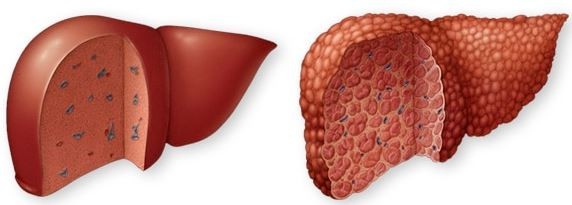

이런 간이 굳어져서 문제가 생기는 것을 간경화, 또는 간경변이라 의합니다. 일반인들은 주로 간경화라 말하고, 의료진이 보통 간경변이란 용어로 활용하고 있고 있습니다. 즉 간이 딱딱하게 굳어져 간 기능이 낮아지는 간질환을 지칭하는 같은 말입니다.

간경화라 부르든 간경변이라 부르든 간에 간이 강인하게 되면 큰일이 발생한 것이죠. 정상 기능을 가능한 간세포의 수가 적어지면 단백질 합성, 해독작용 등 간 기능에 장애가 유발되고, 간이 굳어져 간내 혈액순환이 참 어려워짐에 따라 간 문맥압이 높이고, 황달, 위장관 출혈, 복막염, 간성 혼수, 복수, 하지 부종 등 여러 합병증이 일어합니다.